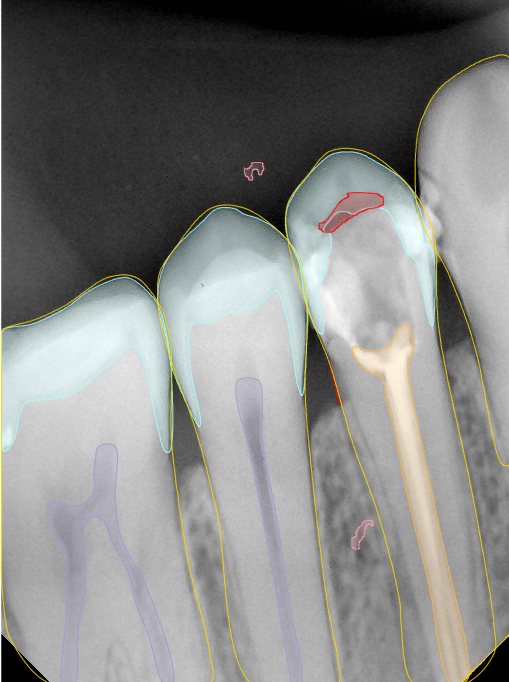

CR/DR 牙齿分割阶段记录

当前进展

- 完成了 CR/DR 牙齿相关分割训练

- 当前结果已经达到阶段预期,但仍有细节问题需要继续处理

相关测试

遇到的问题

- 训练过程中出现过 mask 下移问题

- 部分结果会出现 box 填充异常

- mask 边缘仍然有比较明显的锯齿感

参考

第二版算法问题测试